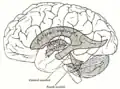

Każda z obu półkul mózgu zawiera w sobie jedną komorę boczną posiadającą łukowaty kształt, przypominający przechyloną nieco w dół literę „C”. W komorach bocznych wyróżnia się rogi przednie (cornu anterius ventriculi lateralis) sięgające do płatów czołowych, rogi dolne (cornu inferius) w płatach skroniowych, rogi tylne (cornu posterius) w płatach potylicznych oraz części środkowe. Komory boczne poprzez otwory międzykomorowe (foramina intraventricularia) łączą się z leżącą nieco niżej, ale położoną centralnie komorą III, znajdującą się częściowo w obrębie międzymózgowia. W tylnej części komory III rozpoczyna się wąski kanał – wodociąg mózgu, który nie zawiera splotu naczyniówkowego i przebiegając przez śródmózgowie łączy się z leżącą jeszcze niżej, również w linii środkowej, komorą IV. Ostatnia z komór znajduje się pomiędzy tylną częścią pnia mózgu a móżdżkiem. Komora IV posiada dwa otwory boczne (aperturae laterales ventriculi quarti) oraz jeden nieparzysty otwór pośrodkowy (apertura mediana ventriculi quarti), przez które płyn mózgowo-rdzeniowy przechodzi do przestrzeni podpajęczynówkowej.

Schemat ilustrujący stosunki anatomiczne systemu komorowego mózgowia względem powierzchni mózgu.